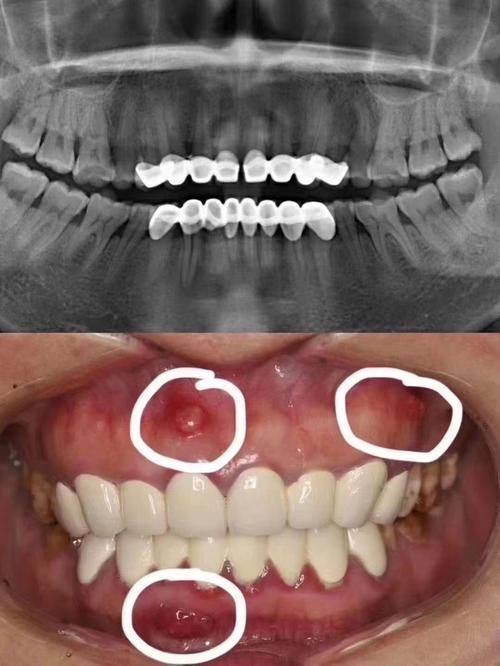

3. 丰富的诊疗项目:涵盖种植牙、牙齿矫正、儿童牙科、牙齿美白、牙周治疗等多个领域,能满足不同患者的口腔需求。

15. 牙周治疗:500 - 2000元

5. 我有牙周炎,在天真口腔诊所进行了牙周治疗。医生技术良好,治疗后牙周炎的症状明显改善。诊所的环境也特别温馨,让人感觉特别放松。